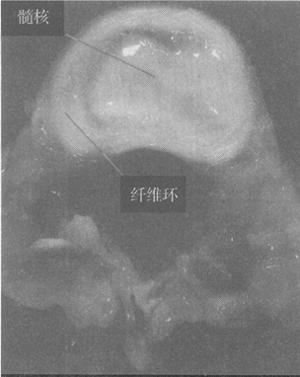

椎间盘由髓核、纤维环和上、下软骨板构成。上、下软骨板紧贴于椎体上、下面;纤维环为围绕于髓核周围的纤维结构,其前份较厚,后外侧份较薄;髓核呈胶状,位于纤维环的中央偏后。椎间盘富于弹性,可缓冲外力对脊柱和颅的震动。

椎间盘由软骨板、纤维环和髓核构成。纤维环由坚硬的致密胶原纤维形成,围绕髓核(图1-29)。

(3)髓核:髓核是一种有弹韧性的液态胶状物质,约占椎间盘切面的50%~60%,位于椎间盘的中央,在下腰椎则偏向后方。髓核含有水分及退化的脊索残余。髓核由软骨样细胞和分散于细胞间的基质组成,并有分化较差且不太致密的胶原纤维网,含大量亲水性氨基葡萄聚糖的胶样凝胶。

髓核的形状由周围的纤维环及上下软骨板所限定,但可随外界的压力改变其位置及形状。髓核的基质和原纤维结构并无一定排列。儿童髓核的结构与纤维环明显划分;老年人由于髓核的纤维变粗,两者的区别则不明显。